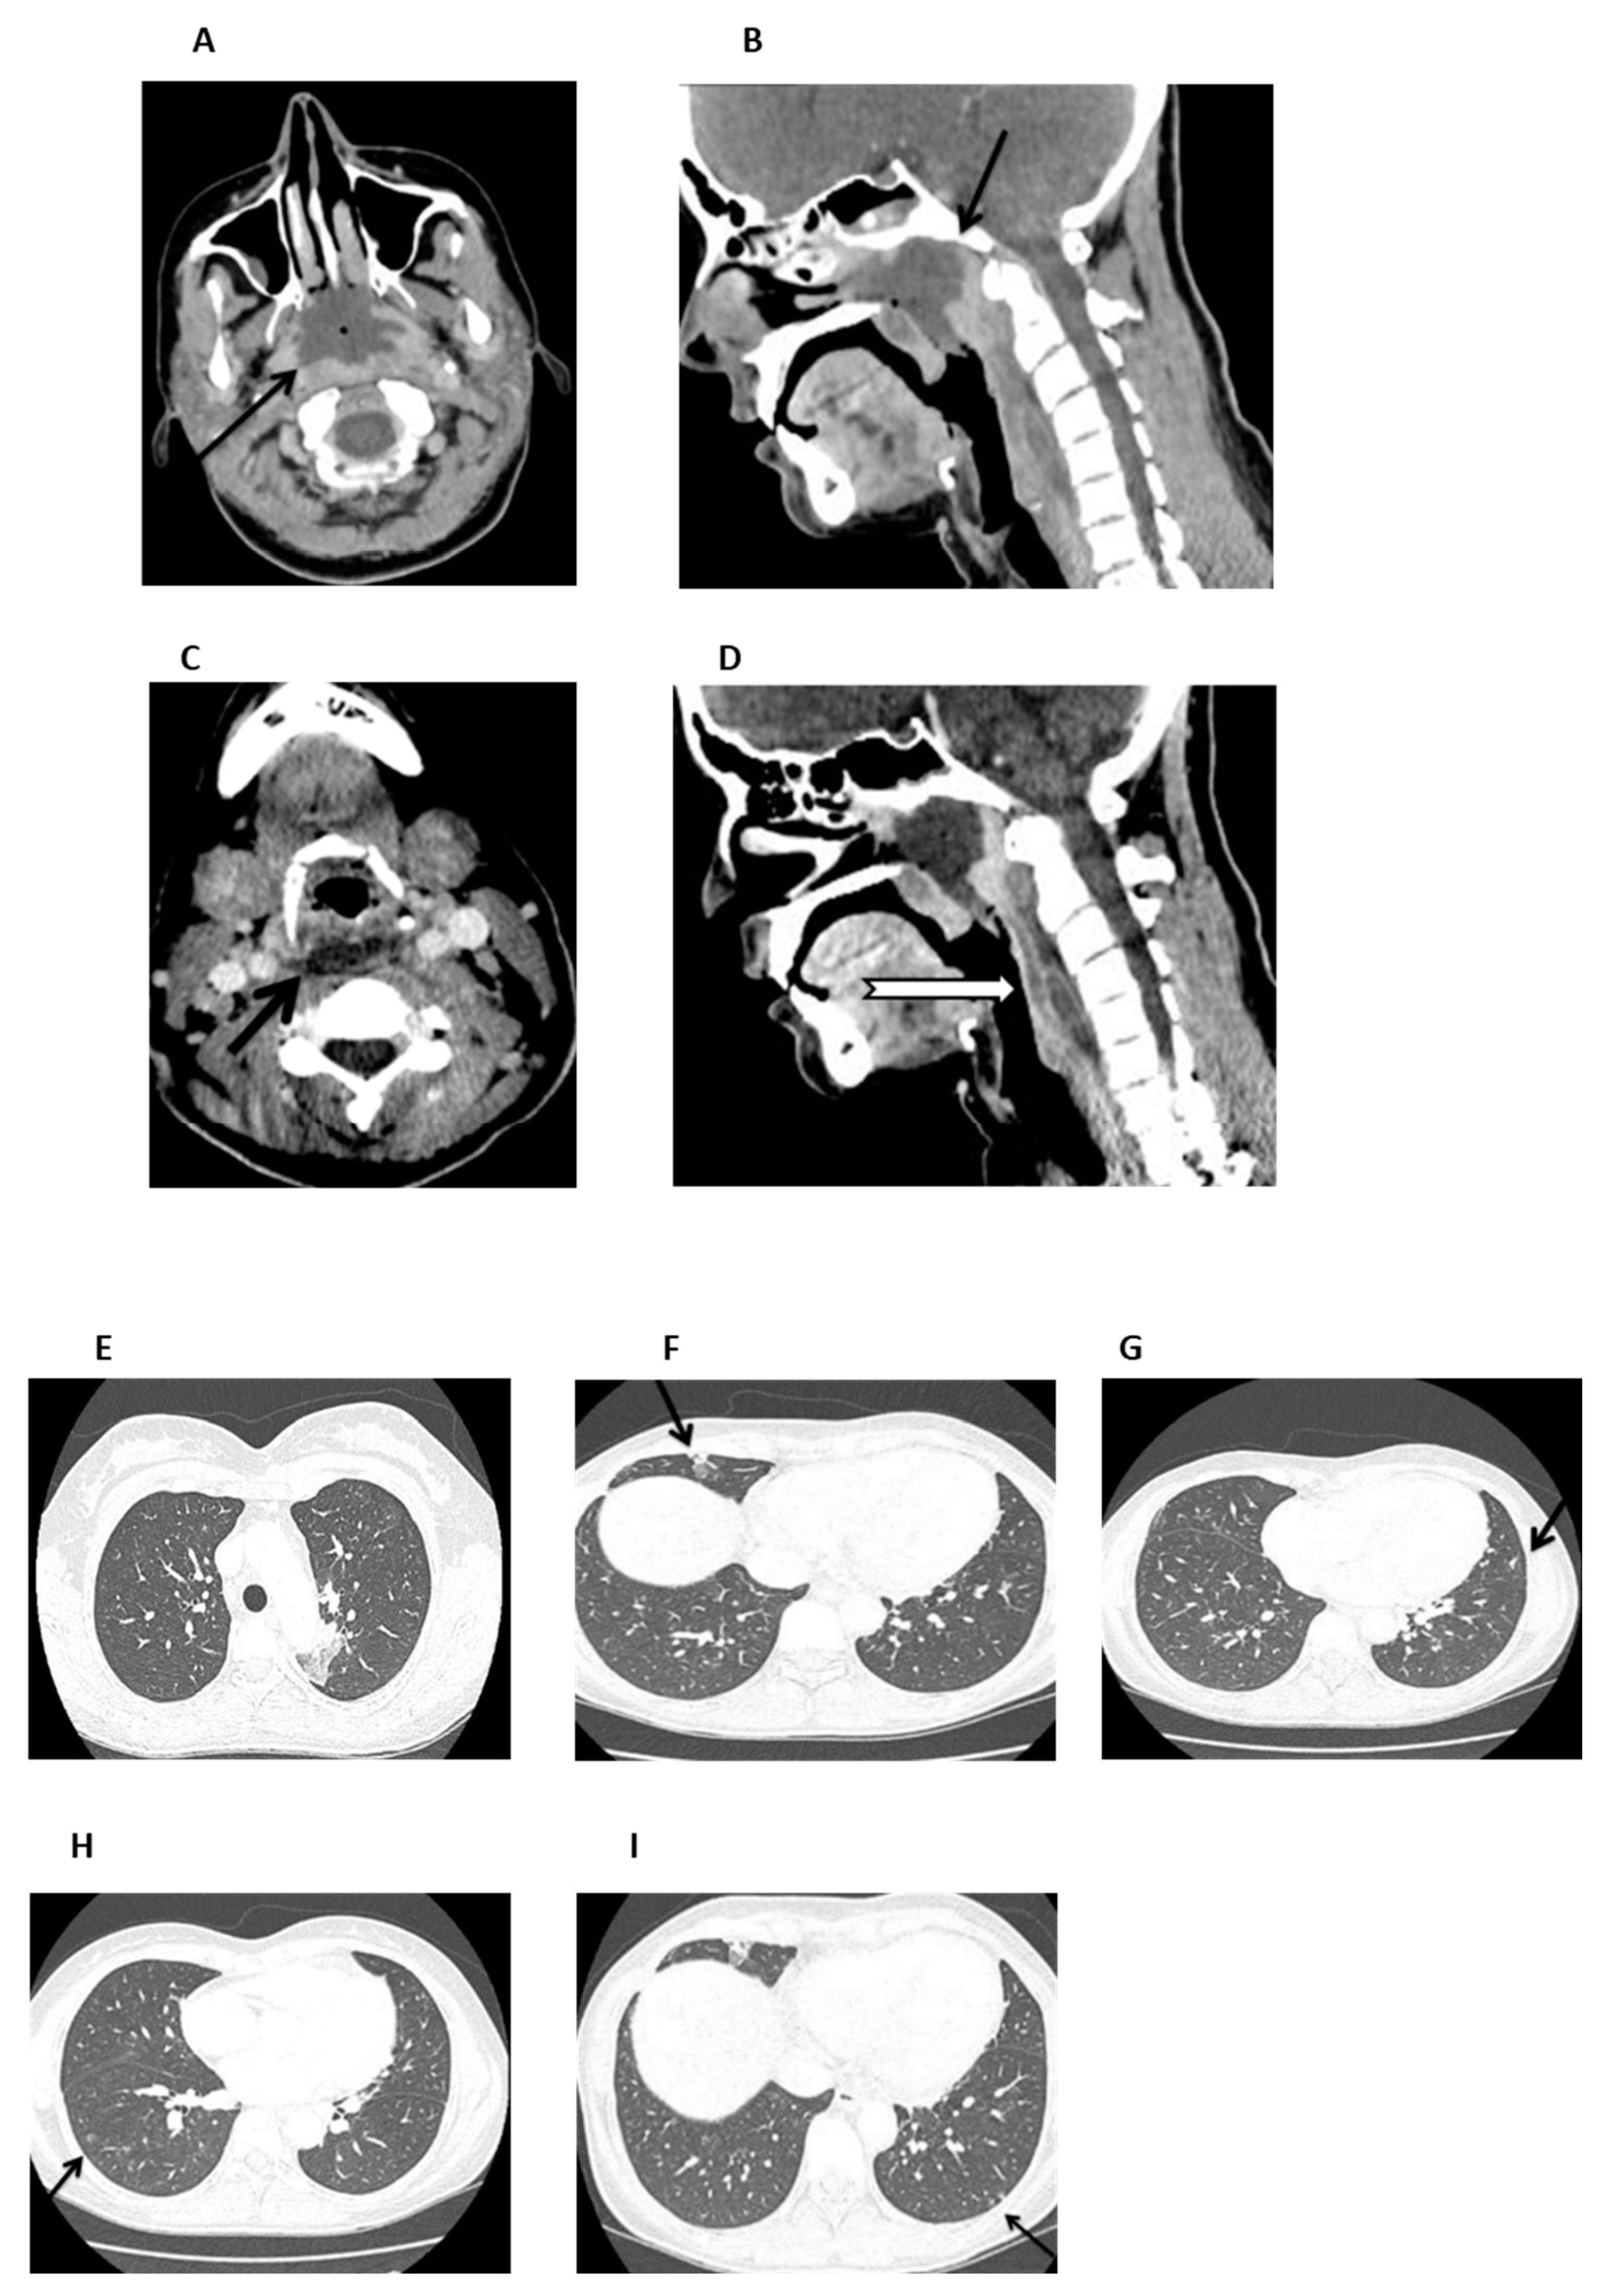

On admission (day +37), the patient was febrile and ill-appearing (Figure 2). She complained of a sore throat and difficulty in swallowing and was noted to have a “hot potato” voice. A deep-neck space infection was suspected and urgent ear–nose–throat (ENT) consultation and imaging studies were ordered. Head CT scan was normal, whereas neck CT scan revealed both nasopharyngeal and retropharyngeal abscesses, with the latter extending into the deep neck spaces (Figure 3A–D). A chest CT scan demonstrated consolidations in the left upper lobe and right middle lobe (Figure 3E,F), centrilobular nodules with tree-in-bud pattern (Figure 3G), along with few predominantly peripheral nodules, some of them with a ground-glass halo (Figure 3H,I).

Figure 3.

Neck and chest CT scan. (A,B). An axial and mid-sagittal image showing a large fluid collection of low attenuation with surrounding rim-enhancement (arrow) and some gaseous foci in the posterior aspect of the nasopharynx (arrow), measuring 3.3 × 4.1 × 2.8 cm, consistent with abscess formation. (C,D). An axial mid-sagittal image depicting another abscess in the retropharyngeal space (arrow) extending from the level of C2 vertebral body, to the C6 level with a craniocaudal diameter of 6.3 cm and a maximum depth of 1 cm, with a significant fat stranding extending into the visceral and carotid spaces, bilaterally. (E,F). Axial images depicting a small consolidation in the apicoposterior segment of the left upper lobe (arrow) and a lobar consolidation with ground-glass opacification in the right middle lobe (arrow). (G). Axial image showing centrilobular nodules with a linear branching pattern (tree-in-bud) in the lower lobes and in the lingula (arrow). (H,I) Axial images showing nodules up to 5 mm, some of them with a ground-glass halo, in the lower lobes (arrow), predominantly peripheral in distribution.